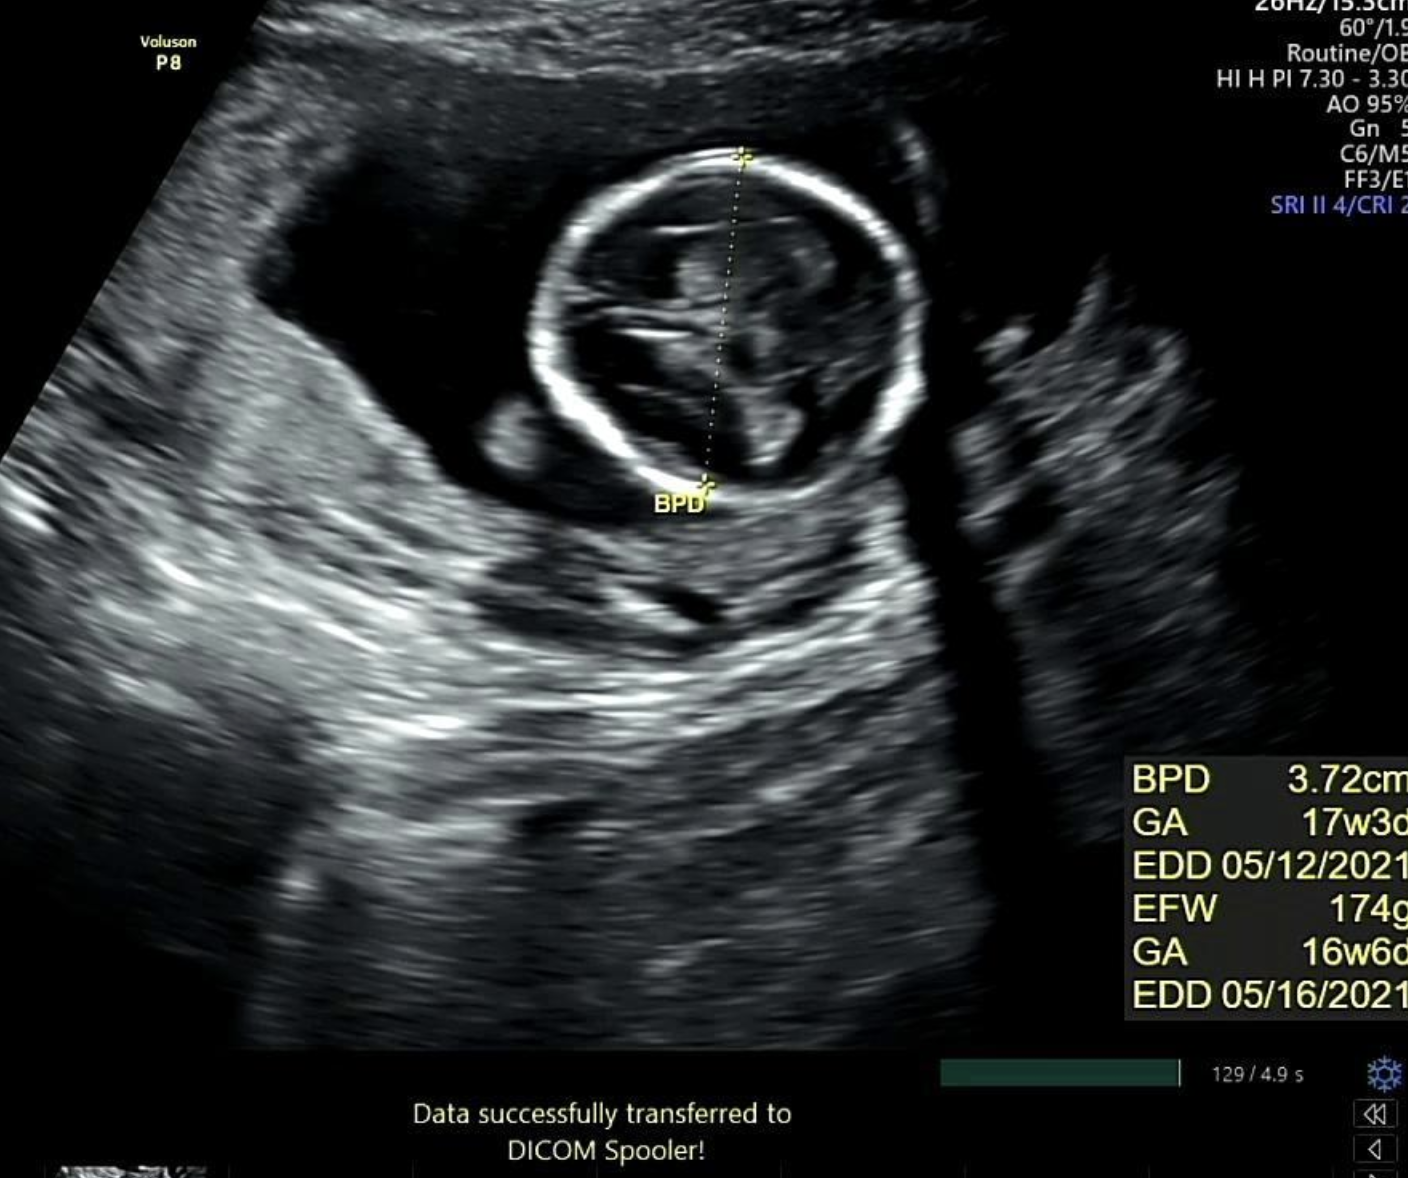

우리의 초음파 영상 데이터는 DICOM 파일이 아닌 단순 녹화본이다. 영상에 대한 메타데이터를 제공받지 못하는 상황이다. 그래서 최초 회의 때 OCR 등을 활용해서 특수문자/숫자 등을 인식시키는 방법 말곤 우리가 원하는 데이터를 직접 측정하고 출력하지 못하는 상황이라고 단정지었다. 객체 인식을 위한 여러 사례와 라이브러리 등을 조사하고 공유했다.

초음파 영상에는 다양한 정보가 있고 영상 내에 용어와 함께 수치/기록 등을 제공하고 있다. 단순하게 ChatGPT 등을 활용해서 우리가 검출하고자 하는 정보 (용어)를 찾을 수 있지만 내 아이 초음파 영상만 하더라도 정보가 (용어) 영상 내에 보이지 않았다. 너무 복불복이었다.

대부분의 녹화본에는 스케일바가 있다. 여기서 픽셀 당 실제거리 (cm/pixel) 을 구할 수 있다고 판단했다. 그래서 내가 원하는 두 점 사이의 거리 (단순 픽셀 거리) 곱하기 cm/pixel 을 곱하면 실제 거리를 구할 수 있다고 생각했다. cm/pixel 이 배율인 셈이다.

실제로는 8.22 cm 로 기록되었고 내가 측정한 기록값은 8.29 cm 로 오차는 크지 않았다. 가설을 검증했고 충분히 해볼 만하고 생각했다. 다만 아래와 같은 해결 과제가 남았다. 첫 번째는 계산 시 (14 cm / 스케일 바 픽셀 거리) 로 하드코딩해서 배율을 계산했기 때문에 스케일 바를 검출하는 이미지 전처리 과정이 필요했다. 두 번째는 초록색 영역 검출 시 곡선과 같은 형태 두 개를 찾고 그 사이 거리를 찾는 식이라 이미지별로 다소 편차가 있었다. 내 눈에는 원처럼 보이는데 컴퓨터가 인식할 때는 원으로 인식하지 않아서 반원 곡선 형태를 찾도록 코딩했다.